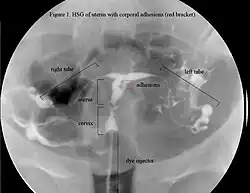

![]() Histerosalpingogram macicy w zespole Ashermana | |

Zespół Ashermana (ang. Asherman's syndrome) – zespół objawów występujący po nadmiernym wyłyżeczkowaniu jamy macicy, gdy powstają w jej wnętrzu bliznowate zrosty zamykające częściowo lub całkowicie światło narządu[1]. Zespół Ashermana może również wystąpić po cięciu cesarskim[2][3], w przebiegu schistosomatozy[4], gruźlicy narządów płciowych[5].

Zrosty powstają w wyniku uszkodzenia błony śluzowej. Główne objawy zespołu to wtórny brak lub skąpe miesiączki[6], bolesne krwawienia, poronienia nawykowe, niepłodność wtórna.